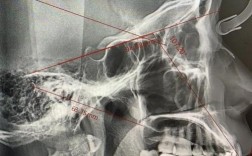

是的,几乎在所有情况下,正畸治疗前都需要拍摄牙片(X光片),这不是一个可有可无的步骤,而是正畸诊断和治疗计划制定的基础和核心,以下是为什么正畸前必须拍牙片的详细原因:全面评估牙齿情况:牙齿数量和位置:确定是否有缺失牙、多生牙(额外牙)、埋...